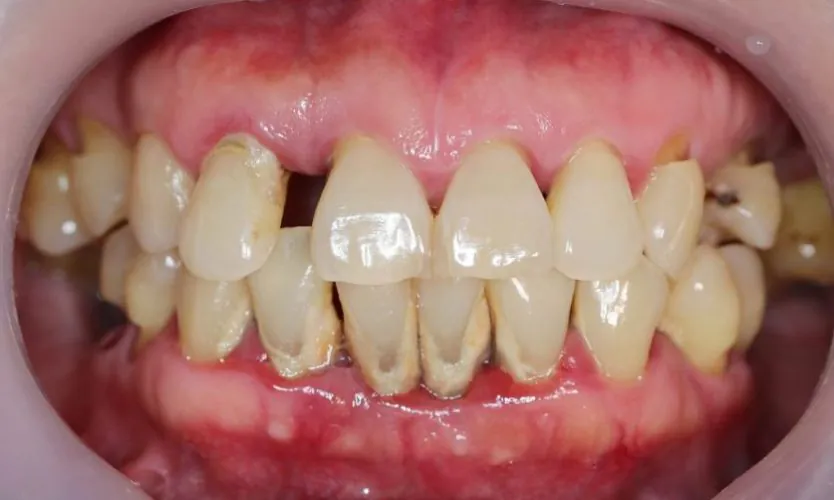

Periodontitis near me is a gum disease in which your gum starts to inflame while causing some severe symptoms including redness, bleeding, or swollen gums. A person should not avoid periodontitis and get Periodontal Disease Treatment for avoiding complications such as tooth loss and tooth decay.

- Inflammation in gums

- Swollen gums

- Redness in gums

- Receding gums,

- Bleeding gums while brushing teeth or flossing

- Loose teeth